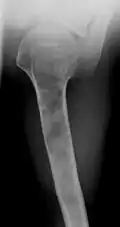

X-ray showing enchondromas localized in the lower part of the radius of a 37-year-old patient affected with Ollier disease -

Abnormal bone growth such as shortening or thickening and deformity may be observed in patients of Ollier disease. These bone lesions are visible at birth using radiography but are usually not screened or examined for until clinical manifestations present during early childhood. However, some patients may exhibit no signs of any symptoms.[1] One study found thirteen to be the mean age of diagnosis in patients with Ollier disease. In an X-ray, there would normally be the presence of several homogeneous lesions of an oval or elongated shape with bone edges that are slightly thickened.[3] With age, these lesions may calcify and appear as diffusely minute spots or stippled. Fan-like septations or streaks would be indicative of the presence of several enchondromas. Early detection and consistent and repeated monitoring is important in order to prevent and treat any potential bone neoplasms.